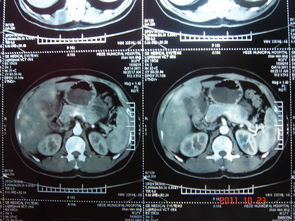

CT掃描通常獲得的是人體橫斷面圖像,但有些病變需要在冠狀位、矢狀位或三維下呈現(xiàn)更能有表現(xiàn)力,更能說明某些情況。如CT血管成像、三維成像、透明化處理等等。

多方位和三維重組也被作為圖像的后處理,實(shí)際上它們都是在橫斷面掃描的基礎(chǔ)上,經(jīng)圖像后處理后的不同方式顯示圖像的一種功能。一般根據(jù)需要,橫斷面圖像可組成冠狀面、矢狀面、斜面或任意曲面的圖形,這被稱為多方位重組。多方位重組的優(yōu)點(diǎn)是:首先是能夠觀察到特定的解剖結(jié)構(gòu),其次是能夠幫助確定病變或骨折等的范圍大小,有助于診斷。而其最大的缺點(diǎn)是由于在橫斷面掃描的基礎(chǔ)中重組,其圖像質(zhì)量受橫斷面掃描圖像質(zhì)量的影響。在三維重組方式中,通過橫斷面圖像的重組可獲得逼真的、立體感的顯示。這種組建方式和多位重組一樣,都需在薄層掃描的基礎(chǔ)上,才能獲得比較滿意的圖像,通常掃描層厚越薄,重組的效果越好。